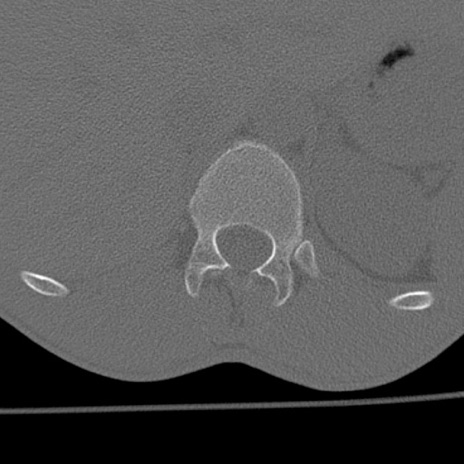

症例3 腰椎CT(横断像)

腰椎CT